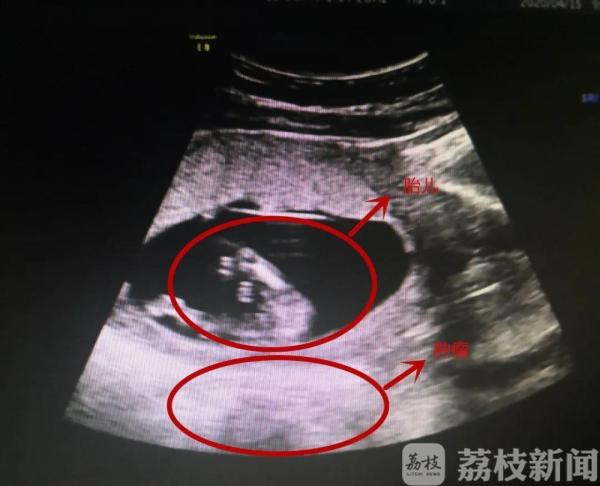

胎儿在母亲体内正常发育,旁边竟然还有一个直径10厘米的肿瘤,这个“要命”的威胁必须要手术解决!5月7日,从手术室里出来的医生坦言,终于体会到了什么叫“心提到了嗓子眼”。

前段时间,淮安市民赵女士被医生告知了两个消息,让她又喜又怕。好消息是她怀孕了,坏消息是她的盆腔里还有一个直径10厘米左右的肿瘤,建议她到上级医院就诊。这肿瘤是什么性质?孩子会保不住吗?赵女士陷入了纠结。

在淮安市妇幼保健院,医生再次为赵女士做了全面检查,发现这个肿瘤位于子宫后方,而且和子宫紧密贴合,如果不及时手术摘除,到了孕晚期会发生危险。“孕晚期子宫越来越大,胎儿也会活动,那么有可能压破肿瘤,引起肿瘤的扭转,一旦肿瘤破裂就会出现腹膜的刺激症状,腹腔的内出血,甚至出现感染、休克,严重会引发流产甚至是胎死宫内的后果。”淮安市妇幼保健院妇科主任医师冒福云说。

尽管做了详细的术前分析,但是在术中,医生发现实际情况要比预判的复杂得多,稍有闪失孩子就可能保不住了。“孕妇怀孕接近14周,子宫比较大,血运丰富,而且这个肿瘤位于子宫的后方,紧贴着子宫,我们几乎没有什么操作空间,要摘除肿瘤就必须移动子宫,移动的过程中可能会刺激子宫引发宫缩造成流产,所以我们就尽量保护周围组织采用一个小切口把肿瘤里面的液体吸出来,减少肿瘤的体积,慢慢游离出来,这样保护了子宫也保护了胎儿。”冒福云告诉记者,手术过程有惊无险,医生精准、轻柔的操作保证了手术的顺利,最终病理结果显示这是一个良性的卵巢畸胎瘤。“术后我们用了一些药物缓解腹部疼痛以及抑制宫缩,另外用了一些补液保证孕妇和胎儿的营养,目前胎儿和产妇情况良好。”